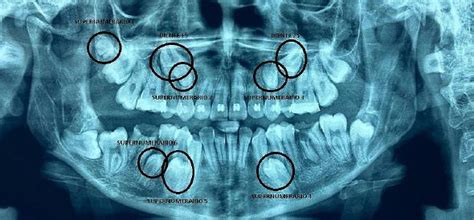

Los dientes supernumerarios son dientes adicionales que exceden el número habitual en la dentición normal, apareciendo donde no deberían.

Estos dientes adicionales ocupan un espacio no previsto, y el 90% de los casos se encuentran en el maxilar superior, entre los incisivos y los caninos, aunque también pueden ser premolares y molares.

Los dientes supernumerarios son considerados una anomalía dental y pueden presentarse de diferentes formas.

Clasificación según su localización

De acuerdo con su localización pueden clasificar en:

- Mesiodens: Éstos se encuentran entre los incisivos centrales superiores, puede ser único, múltiple, unilateral o bilateral, erupcionado o impactado, vertical, horizontal o invertido, suelen presentarse también en la zona mandibular.

Las complicaciones asociadas con un mesiodens incluido son: retraso de erupción del diente permanente, desviación de la erupción del diente, retención, reabsorción de la raíz del diente permanente y diastema.

- Paramolar: Molar supernumerario pequeño y rudimentario, situado bucal o lingualmente a un molar maxilar o en el espacio interproximal entre el segundo y tercer molar.

- Distomolar: Se localiza en la cara distal del tercer molar, es pequeño, rudimentario y raramente impide la erupción normal de los dientes.